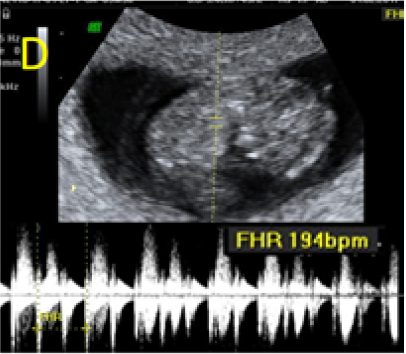

A 22-year-old secundigravida, presented to our Hospital with acute pelvic pain and vaginal bleeding. Her medical history included a 2-year prior caesarean delivery. The patient was in a stable condition and the clinical exam was unremarkable. As the urinary pregnancy test was positive, a transvaginal ultrasound scan was performed to evaluate the pregnancy location and viability. The exam revealed an empty uterine cavity but identified the gestational sac at the level of the caesarean scar with a live embryo (174 beats per minute), measuring 8 weeks and 5 days by crown-rump length. (Figures 1). Because the trophoblastic tissue was noted with an anteriorly location, urinary bladder invasion was suspected based on the ultrasonographic signs: poor identification of the bladder wall, the lack of the sonolucent space and increased vascularization with abnormal pattern (Figure 2). The patient blood tests results were normal, and beta-human chorionic gonadotropin (b-HCG) value was 145.000mUI/ml. After proper counselling and written informed consent the patient opted for a medical conservative treatment with desire to preserve her fertility.

Figure 1. A: the gestational sac is located at the level of the uterine isthmic scar, grey-scale and Power Doppler transvaginal evaluation. B: an embryo with a crown-rump length (CRL) that corresponds to 8 weeks and 1 day is found with normal fetal heart activity (C).